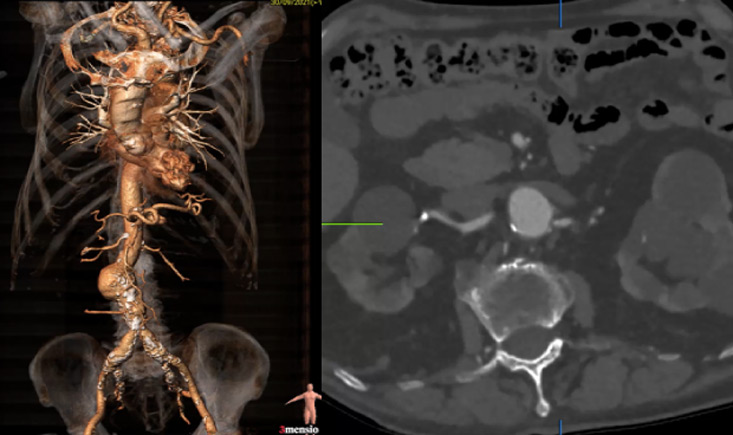

On angio-CT 2024: persistence of EL2, with sac growth (59 mm).

- Sac growth.

- Correct sealing.

- Endoleak lateralised to cava